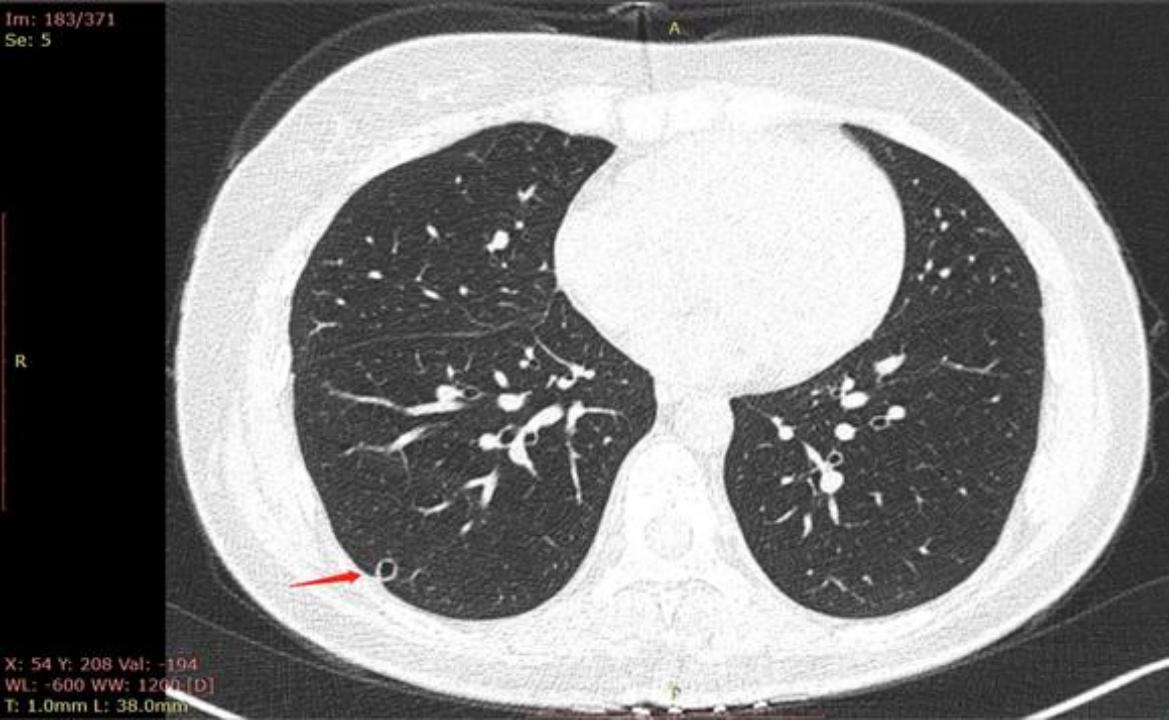

2022年7月29日去同一家A医院复查拍CT,检查结果如下,四个月后,结节从1.2变成了1.9 cm,发现结节长这么快,真的很慌,我老公不抽烟不喝酒,身体一直比较健康,没有住过院都,也没有家族史,不知道一下就长这么大一个结节,求助各位病友,各位医生,还有敬爱的戴主任,麻烦各位有经验的帮忙看看,我们目前只看上一个北京三甲医院普通号的大夫,大夫只说磨玻璃不应该长这么快,长的挺奇怪,不典型,其他没说什么,还没挂上其他医院的号,先麻烦各位帮忙看看,万分感谢!

CT截图: